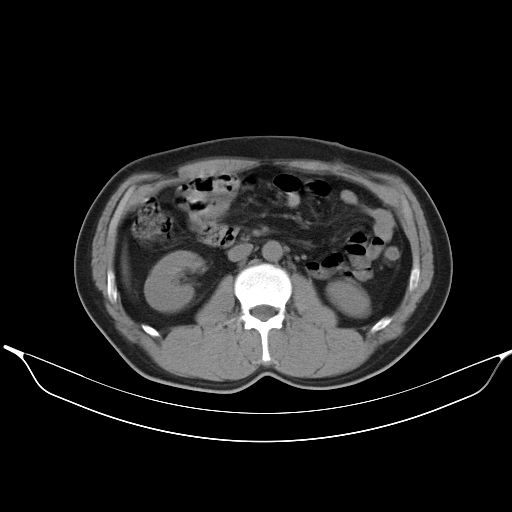

标题: CT25490:男,40岁,体检发现;无其它不适。 [打印本页]

标题: CT25490:男,40岁,体检发现;无其它不适。

考虑右下肺周围性肺癌并肺内多发转移,纵隔淋巴结转移!

支持 !考虑右下肺周围性肺癌并肺内多发转移,纵隔淋巴结转移,(气管前腔静脉后,隆突下,主动脉弓下都有了)

1、均为转移,原发灶不在肺内。2、肺癌肺转移。